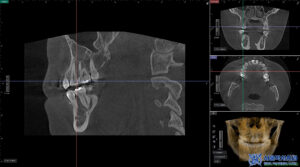

또한 정밀한 확인을 위해

3D CT를 촬영하였습니다.

위쪽 치아 뿌리 끝 염증을

확인할 수 있었습니다.

이에 따라 단순한 충치 치료가 아닌,

감염된 신경을 제거하고

염증을 정리하는 신경치료를

우선적으로 진행하여

가능한 한 자연치아를 살리는 방향으로

치료 계획을 세웠습니다.